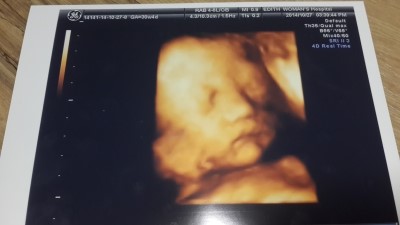

임신 30주 4일 증상 / 입체초음파 / 배크기